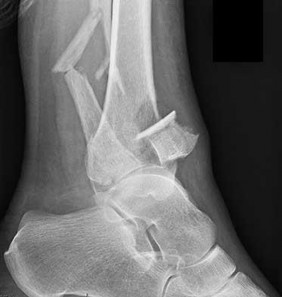

A 35-year-old female sustains a twisting injury to her ankle. Radiographs reveal a transverse fracture of the medial malleolus and a spiral fracture of the proximal third of the fibula (Maisonneuve fracture). For this specific fracture pattern to occur, which of the following ligamentous structures MUST be completely disrupted?

A Maisonneuve fracture is a pronounced variation of a pronation-external rotation (PER) injury. The mechanism involves external rotation of the talus, which either avulses the medial malleolus or ruptures the deltoid ligament, then disrupts the anterior inferior tibiofibular ligament, tears up the interosseous membrane all the way to the proximal fibula, and exits as a high fibular fracture. Therefore, the syndesmotic complex and the interosseous membrane up to the level of the fracture are intrinsically disrupted.